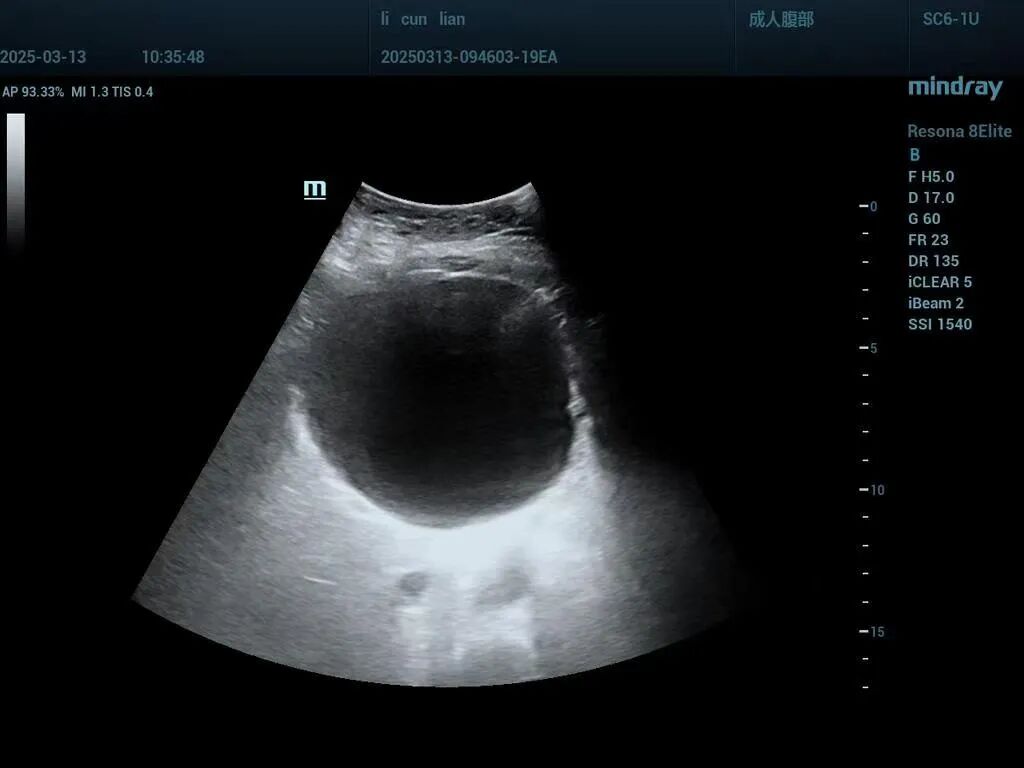

图片

手术前(肝囊肿直径约11cm)